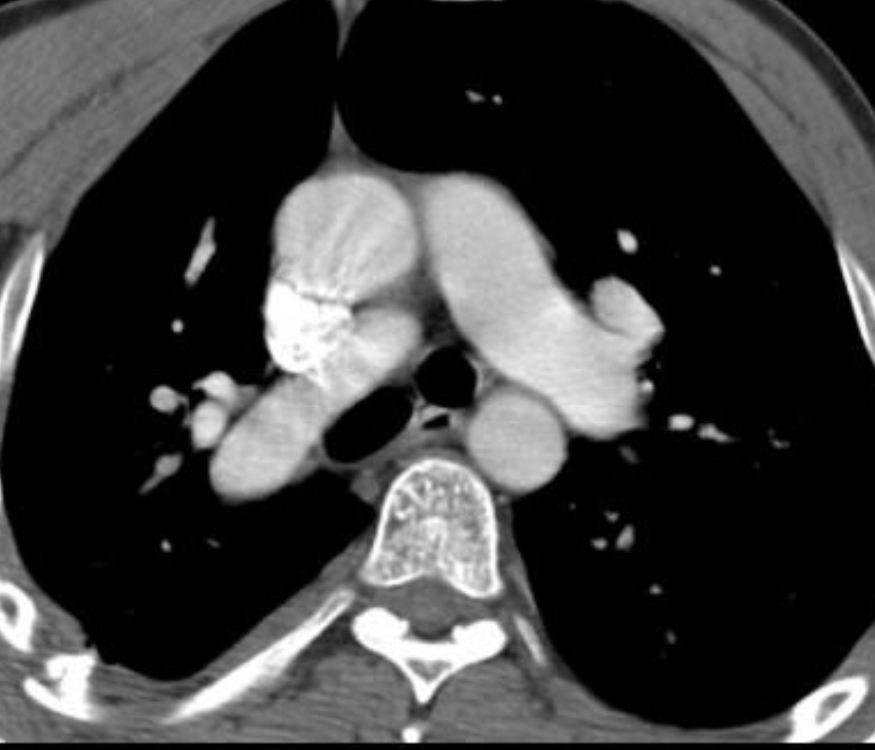

Lymphangioleiomyomatosis (LAM)

Large thin-walled cysts diffusely distributed in the lungs that will eventually replace the entire lung parenchyma.

exclusive to women of child-bearing age, except for TS associated in men

–lymphangiomas and AMLs are commonly associated.

–A/w chylothorax

49 year old woman with a rash on her face. CT chest with multiple thin walled cysts

LAM

a/w renal AMLs and LAD, seen here

Almost exclusively middle aged women although can also occur in TS

p/w exertional dyspnea, recurrent PTX is common